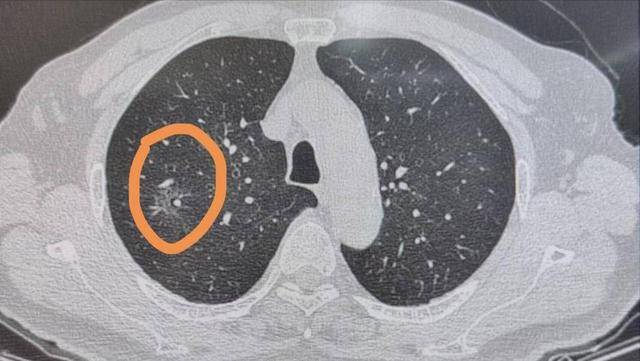

医生通常会建议,如果第一次复查稳定,那么间隔时间可以延长,但一年这个节点必须得查。尤其是那种磨玻璃结节,这种结节在影像上看起来比较轻淡,不像实性结节那样容易一眼辨别,但它们往往更“隐蔽”,潜在恶性的比例更高。

很多磨玻璃结节的恶变过程是“按年计算”的,不少临床病例中,早期的原位腺癌或者微浸润性腺癌,就是在一年甚至更久的观察中才被发现的。

-   磨玻璃结节的特殊性:磨玻璃结节(GGN)是一种特殊的肺结节类型,其恶性风险相对较高,尤其是持续存在的纯磨玻璃结节或部分实性磨玻璃结节。这类结节的恶变过程往往较为缓慢,“按年计算”。

-   重新评估的机会:一年后的复查可以观察结节在较长时间内的变化。如果一年内结节依然稳定,无增大、密度无增加、边缘无明显变化,则良性可能性进一步增加。若出现轻微形态改变(如边缘模糊、密度加深、出现实性成分),则需提高警惕。